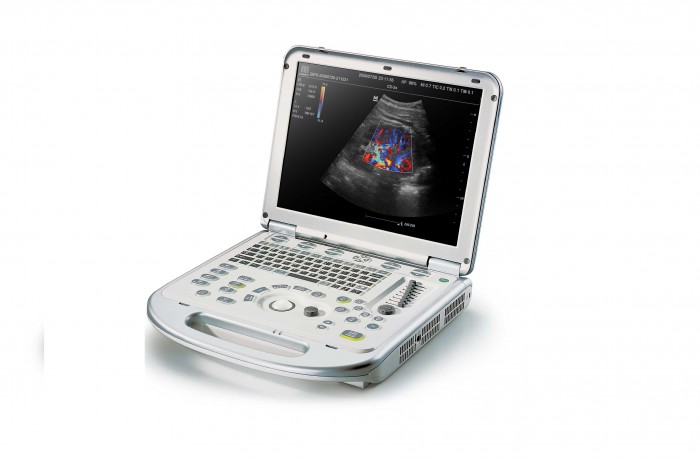

Mindray M7/M6 je dopplerovský ultra ľahký prenosný UZV prístroj strednej triedy s použitím HD sond. Stress echo. 4D. TDI. Panoramatické zobrazenie...

- 15“ High resolution LCD monitor / 320 GB HDD/ hmotnosť 6,5 kg